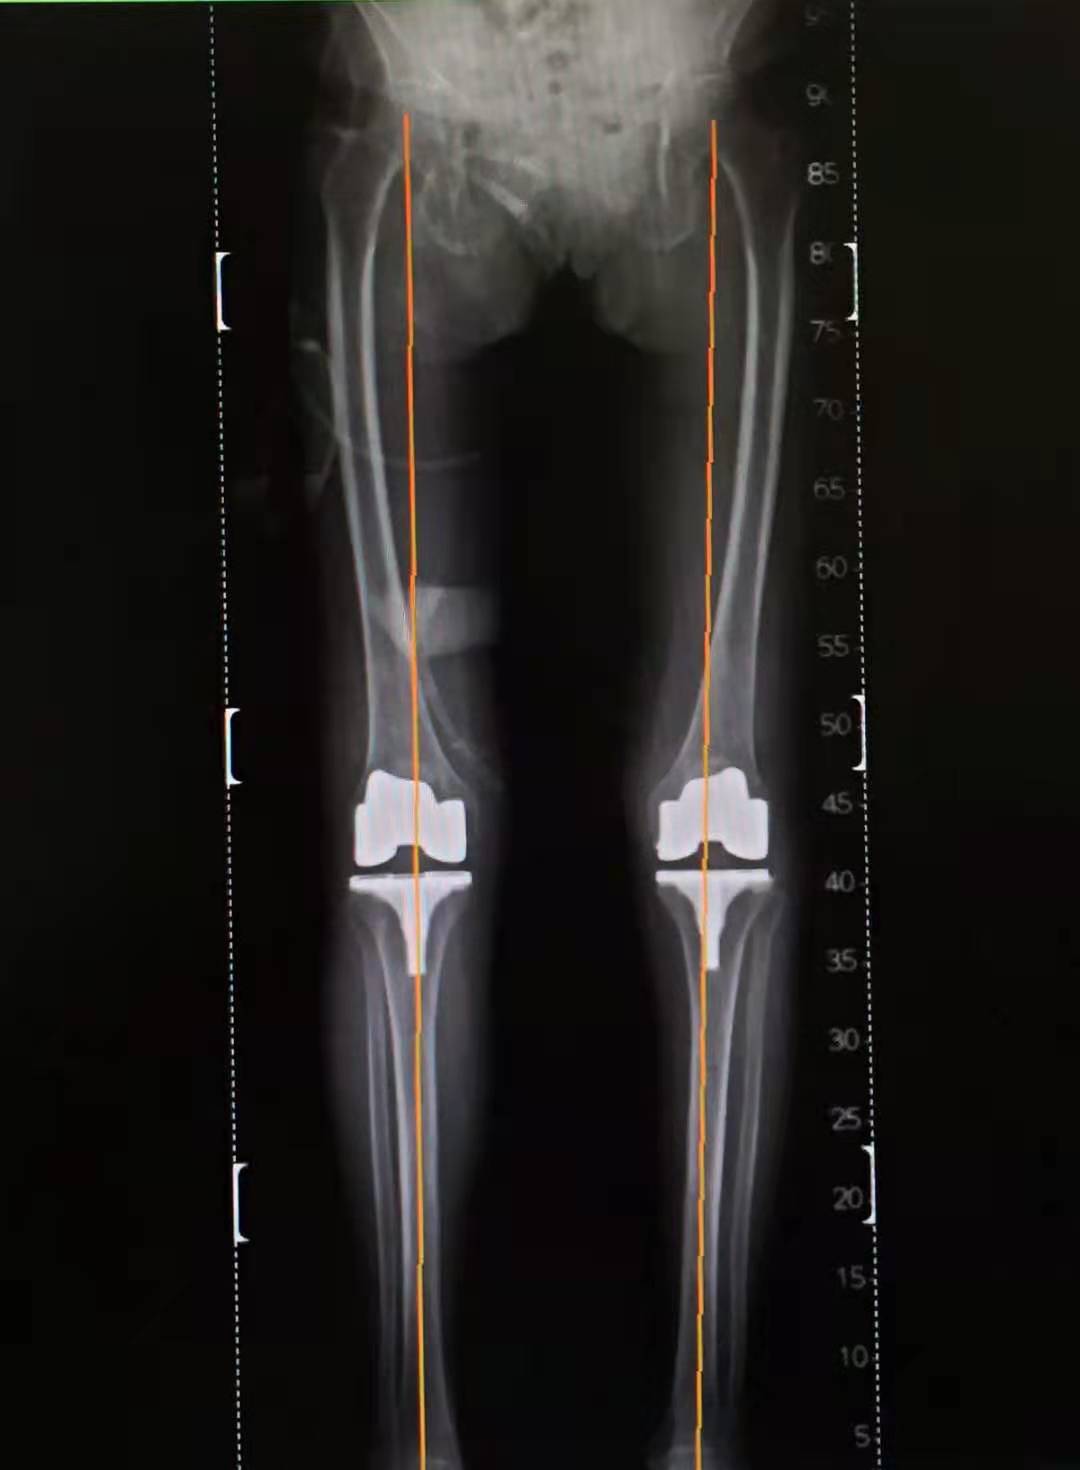

双侧TKA术后的正位片提示膝关节畸形得到纠正

双下肢力线恢复到正常